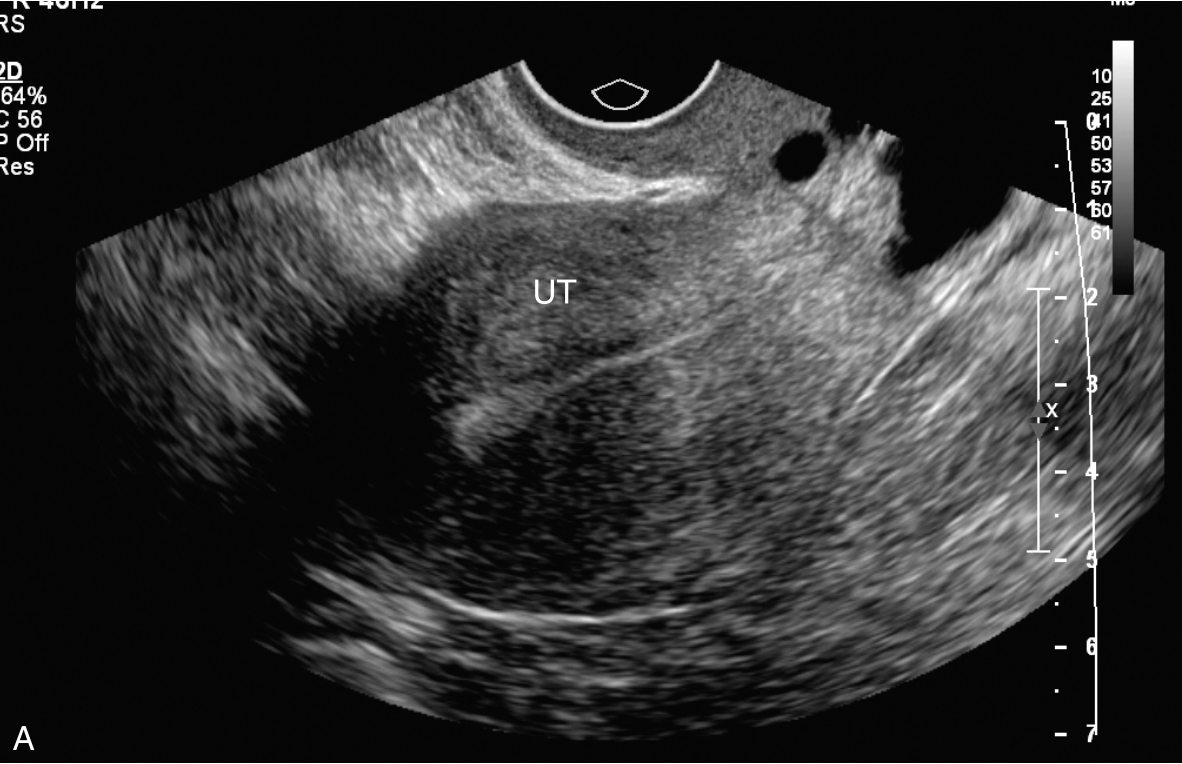

CT检查(入院当天)见图3-12-1,右侧闭孔区淋巴结稍增大,大血管旁未见增大淋巴结;右附件区稍增厚,可见小囊状影。

图3-12-1 盆腔CT图像

A.盆腔子宫底横切面;B.盆腹腔子宫矢状面。UT:子宫。